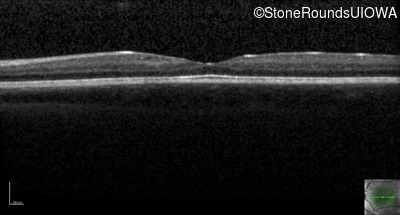

This 6 year old boy first experienced difficulty reading and seeing the blackboard at age 5.

| Age at visit: 6 years |

| Age at visit: 11 years |

| Age at visit: 14 years |

| Age at visit: 14 years (Visit 2) |